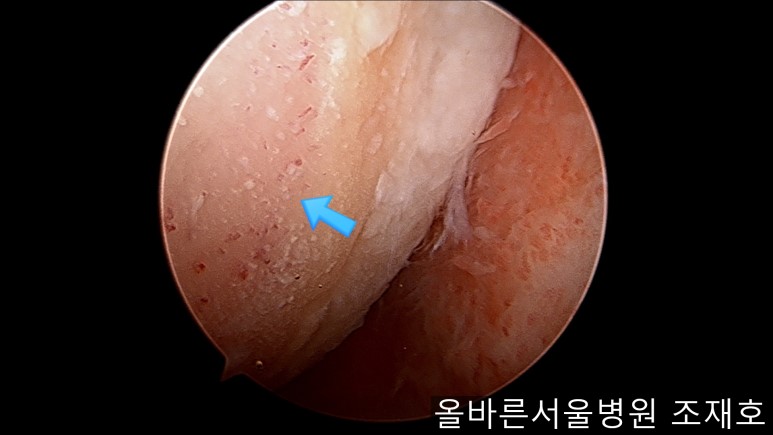

虽然前方十字韧带粘液样变性,但稳定性无异常

前方十字韧带处没有覆盖滑膜的粘液样变性的外观及稳定性无异常。